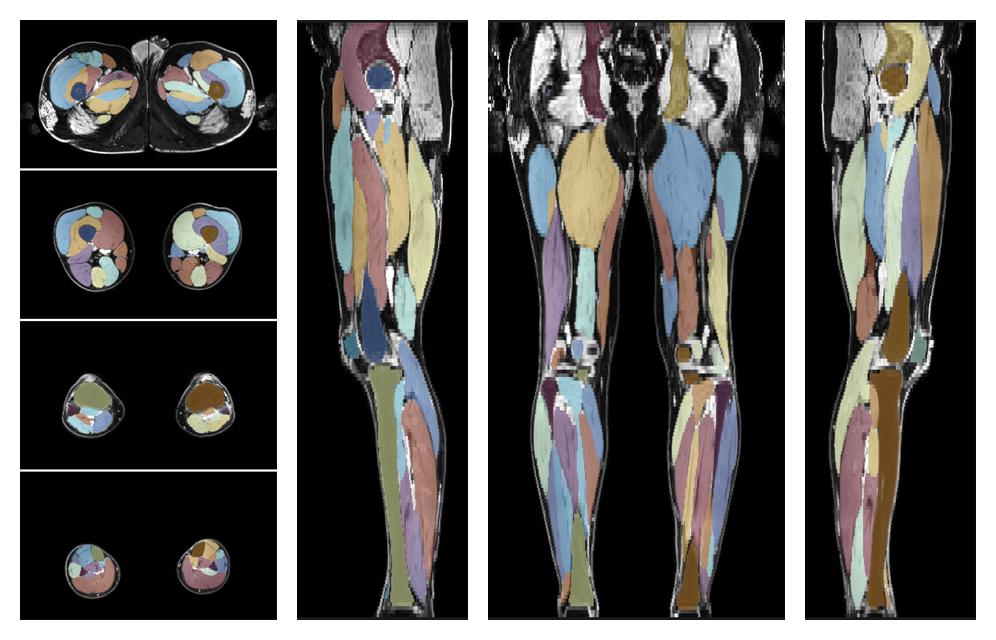

Muscle segmentation

Convolution neural network based (UNET) fiber automated muscle segmentation, for information look here».

• 3D volume render of automated muscle segmentation.

3D render of automated muscle segmentation labels generated using a CNN UNET.

• Automated muscle and bone segmentation.

Overlay of automated muscle segmentation labels on dixon water image.